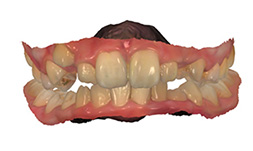

At the records appointment photos and 3D models of the teeth are made, as well as necessary x-rays and a comprehensive oral examination.